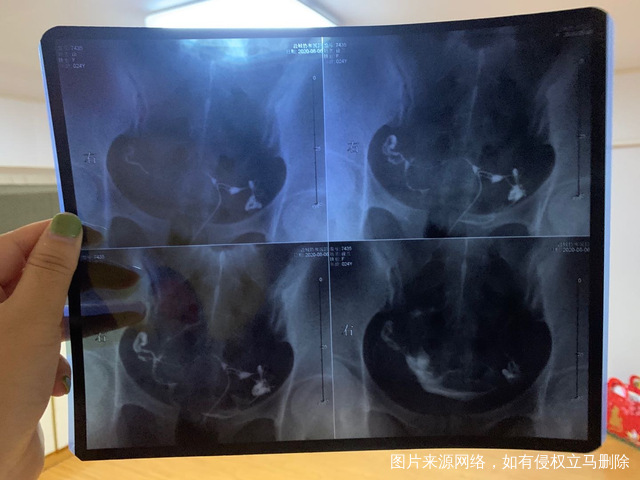

请问一下我这样情况输卵管算严重的嘛我没怀过孕

做完输卵管造影第六天了小腹还是感觉沉甸甸的如

可以热敷腹部,如果有发热,腹痛加剧,白带量多,有异味,随时就医